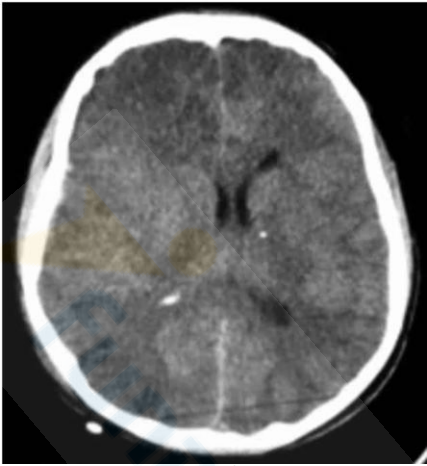

Com base na Figura 1 abaixo, assinale a alternativa que indica a lesão apresentada na tomografia.

Figura 1